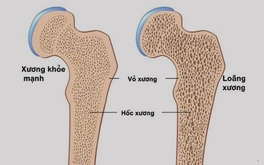

Tên gọi chính thức của hội chứng này là bệnh cơ tim Takotsubo, có thể xảy ra khi người bệnh trải qua cảm xúc cực độ. Ngoài ra, hội chứng "trái tim tan vỡ" cũng có thể xảy ra ở những người có vấn đề về thể chất, chẳng hạn trải qua phẫu thuật hay đột quỵ.

Trong cả hai trường hợp, khi chịu áp lực đột ngột, cơ thể sẽ giải phóng một lượng lớn hormone căng thẳng, chẳng hạn như cortisol và adrenaline, gây áp lực cho tim.